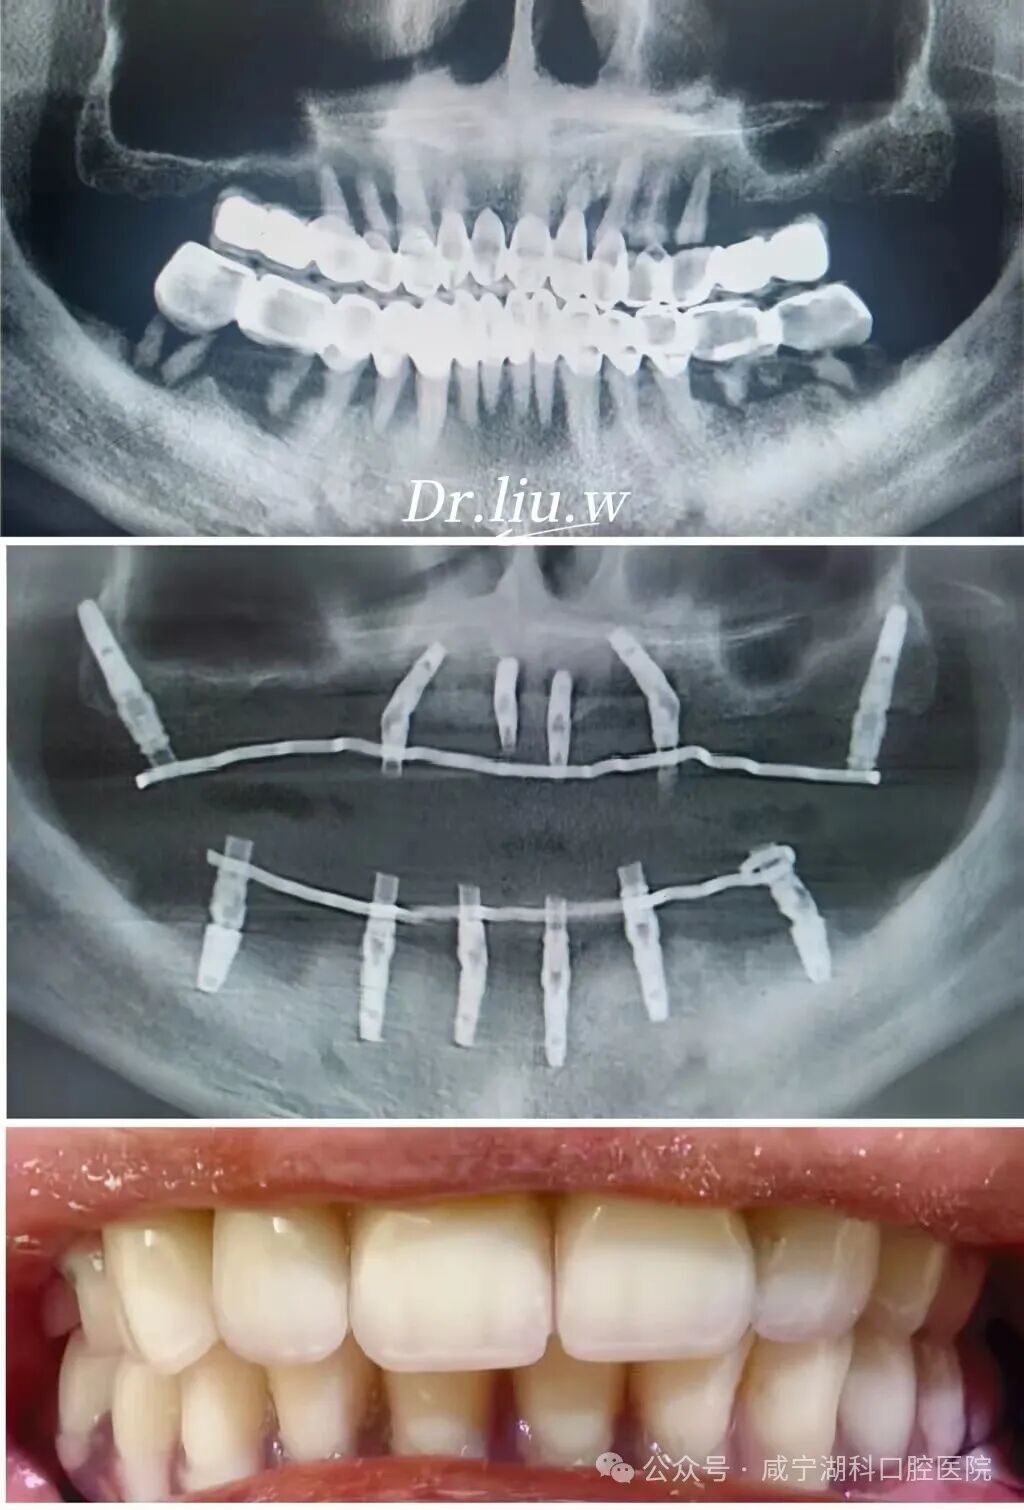

家住崇阳的胡阿姨,因牙齿缺失多颗,说话漏风,常年只能吃一些软烂食物,去过多家医疗机构治疗修复都没有达到效果,还因骨头条件太差被告知无法种植,于是胡阿姨抱着试一试的心态来到湖科口腔医院寻求解决办法。

“想做种植牙,但是他们说我牙槽骨太薄,已经没办法再种了。”胡阿姨回忆道,此刻,她的口腔内,上颌仅剩4颗牙,下颌磨牙全部缺失,严重影响了进食和社交,生活品质一落千丈。

刘伟院长根据胡阿姨的牙齿情况,分析到上颌窦剩余骨量非常少,做种植有两种方式,一种是采用上颌窦外提升,需要大量植骨,要忍受大半年至一年的无牙期,而且要进行两次手术才能完成修复。第二种是穿翼种植,是一种新技术,目前咸宁掌握这项种植技术的医生很少,这项技术是拔完牙后即刻就进行穿翼种植,只用一次手术就能完成种植,当天就能戴牙,大大缩短修复时间,减少无牙痛苦。

经过多方比较,1月25日,胡阿姨最终选择了刘伟院长为她进行穿翼种植,最终当天拔掉上颌两颗松动牙,保留了2颗大磨牙,植入5颗种植体,当天拔牙当天种当天戴固定牙。她说:“毕竟湖科口腔口碑很好,种植牙是很考验医生技术的手术,既然要做,就要找靠谱的、术后维护有保障的医院,技术过硬的医生。”

穿翼种植是一种特殊的口腔种植技术,被誉为种植牙界的“无土栽培术”,手术难度非同一般,临床中适用于上颌牙槽骨极度萎缩、骨量流失严重、重度缺骨等情况,无法进行常规种植牙的患者。

在这种手术中,种植体不是常规地植入牙槽骨,而是穿过上颌窦,把种植体植入到鼻部两侧的翼骨。翼状板位于上颌骨后部,较为坚固,能够提供良好的支撑。这就像是为牙齿的修复搭建了一个超级稳固的 “桥墩”,为牙列缺失或严重损坏的患者提供了一种有效的解决方案。